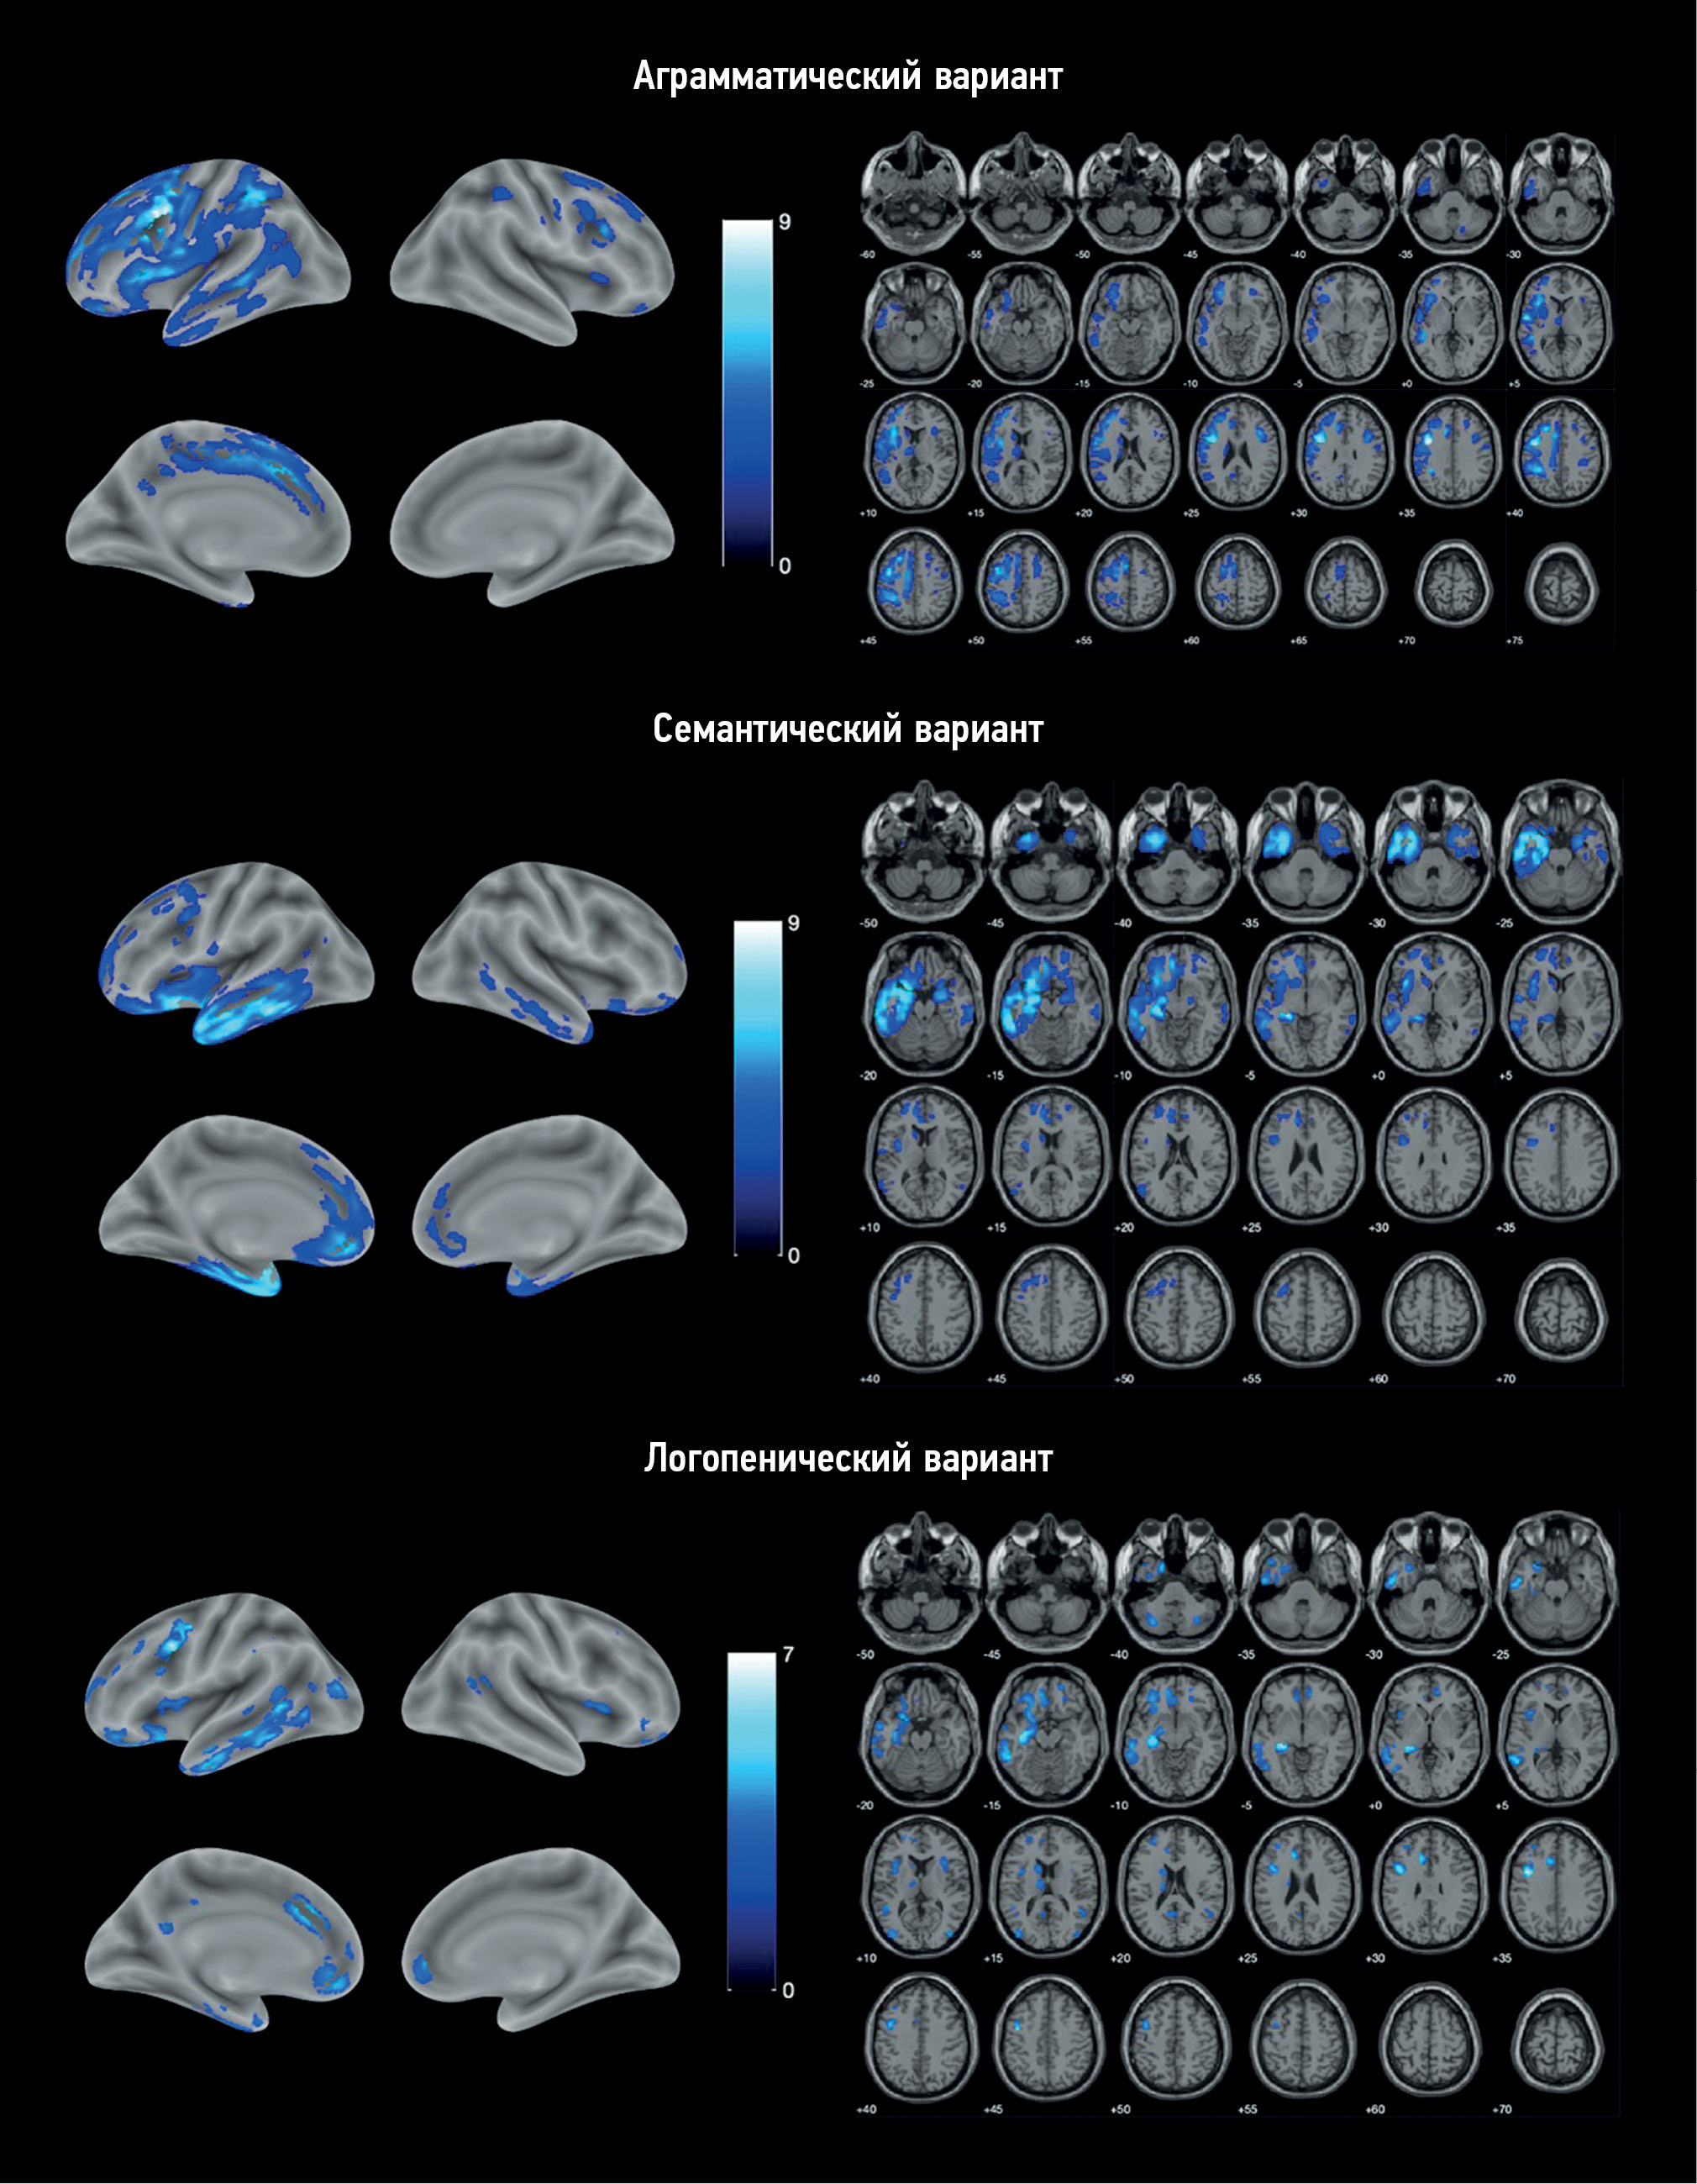

Structural gray matter changes in primary progressive aphasia variants

BACKGROUND: Primary progressive aphasia is a rare neurodegenerative disease with high clinical, genetic, and pathomorphological heterogeneity that greatly complicates its diagnosis. Voxel-based morphometry can be used to objectively assess structural gray matter changes and determine atrophy patterns in variants of primary progressive aphasia, which can improve the diagnosis and our understanding of its pathogenesis.

AIMS: This study aimed to evaluate the patterns of atrophy in each of the primary progressive aphasia variants in comparison with the control group.

MATERIALS AND METHODS: Patients diagnosed with one of the primary progressive aphasia variants, established in accordance with the current diagnostic criteria, were included in the main group. The control group consisted of healthy volunteers without any neurological symptoms or structural brain changes. All participants underwent brain magnetic resonance imaging. The obtained images were processed and used for voxel-based morphometry, which was performed by comparing the gray matter volume between each of the primary progressive aphasia variants and the control group. The study was adjusted for the sex, age, and intracranial volume of the participants.

RESULTS: The study enrolled 25 patients with nonfluent, 11 with semantic, and 9 with logopenic variants of primary progressive aphasia, as well as 20 healthy volunteers. Voxel-based morphometry showed a specific atrophy pattern in each of the variants of primary progressive aphasia, with predominant involvement of the frontal and insular lobes in nonfluent, temporal lobe and hippocampus in semantic, and a more diffuse frontotemporal pattern in logopenic variants.

CONCLUSIONS: The study revealed gray matter atrophy patterns specific to each variant of primary progressive aphasia. The obtained results mainly correspond to the clinical presentations of the disease. Moreover, some findings (e.g., absence of the posterior perisylvian atrophy and reduced motor cortex volume in the logopenic variant, atrophy of the orbitofrontal cortex and cerebellum in the nonfluent variant, and premotor cortex, precentral, and inferior frontal gyrus degeneration in the semantic variant) do not correlate with the usual understanding of primary progressive aphasia pathogenesis and require further study.